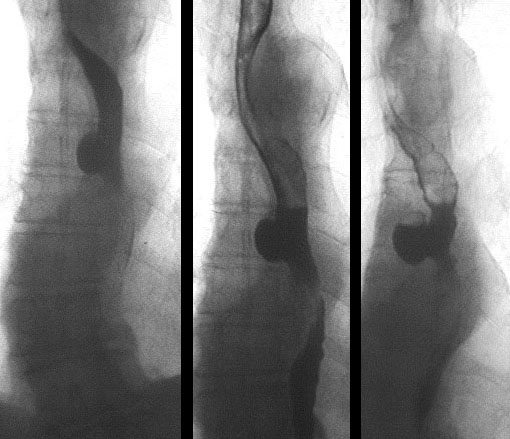

Дивертикулы пищевода при рентгенконтрастном исследовании